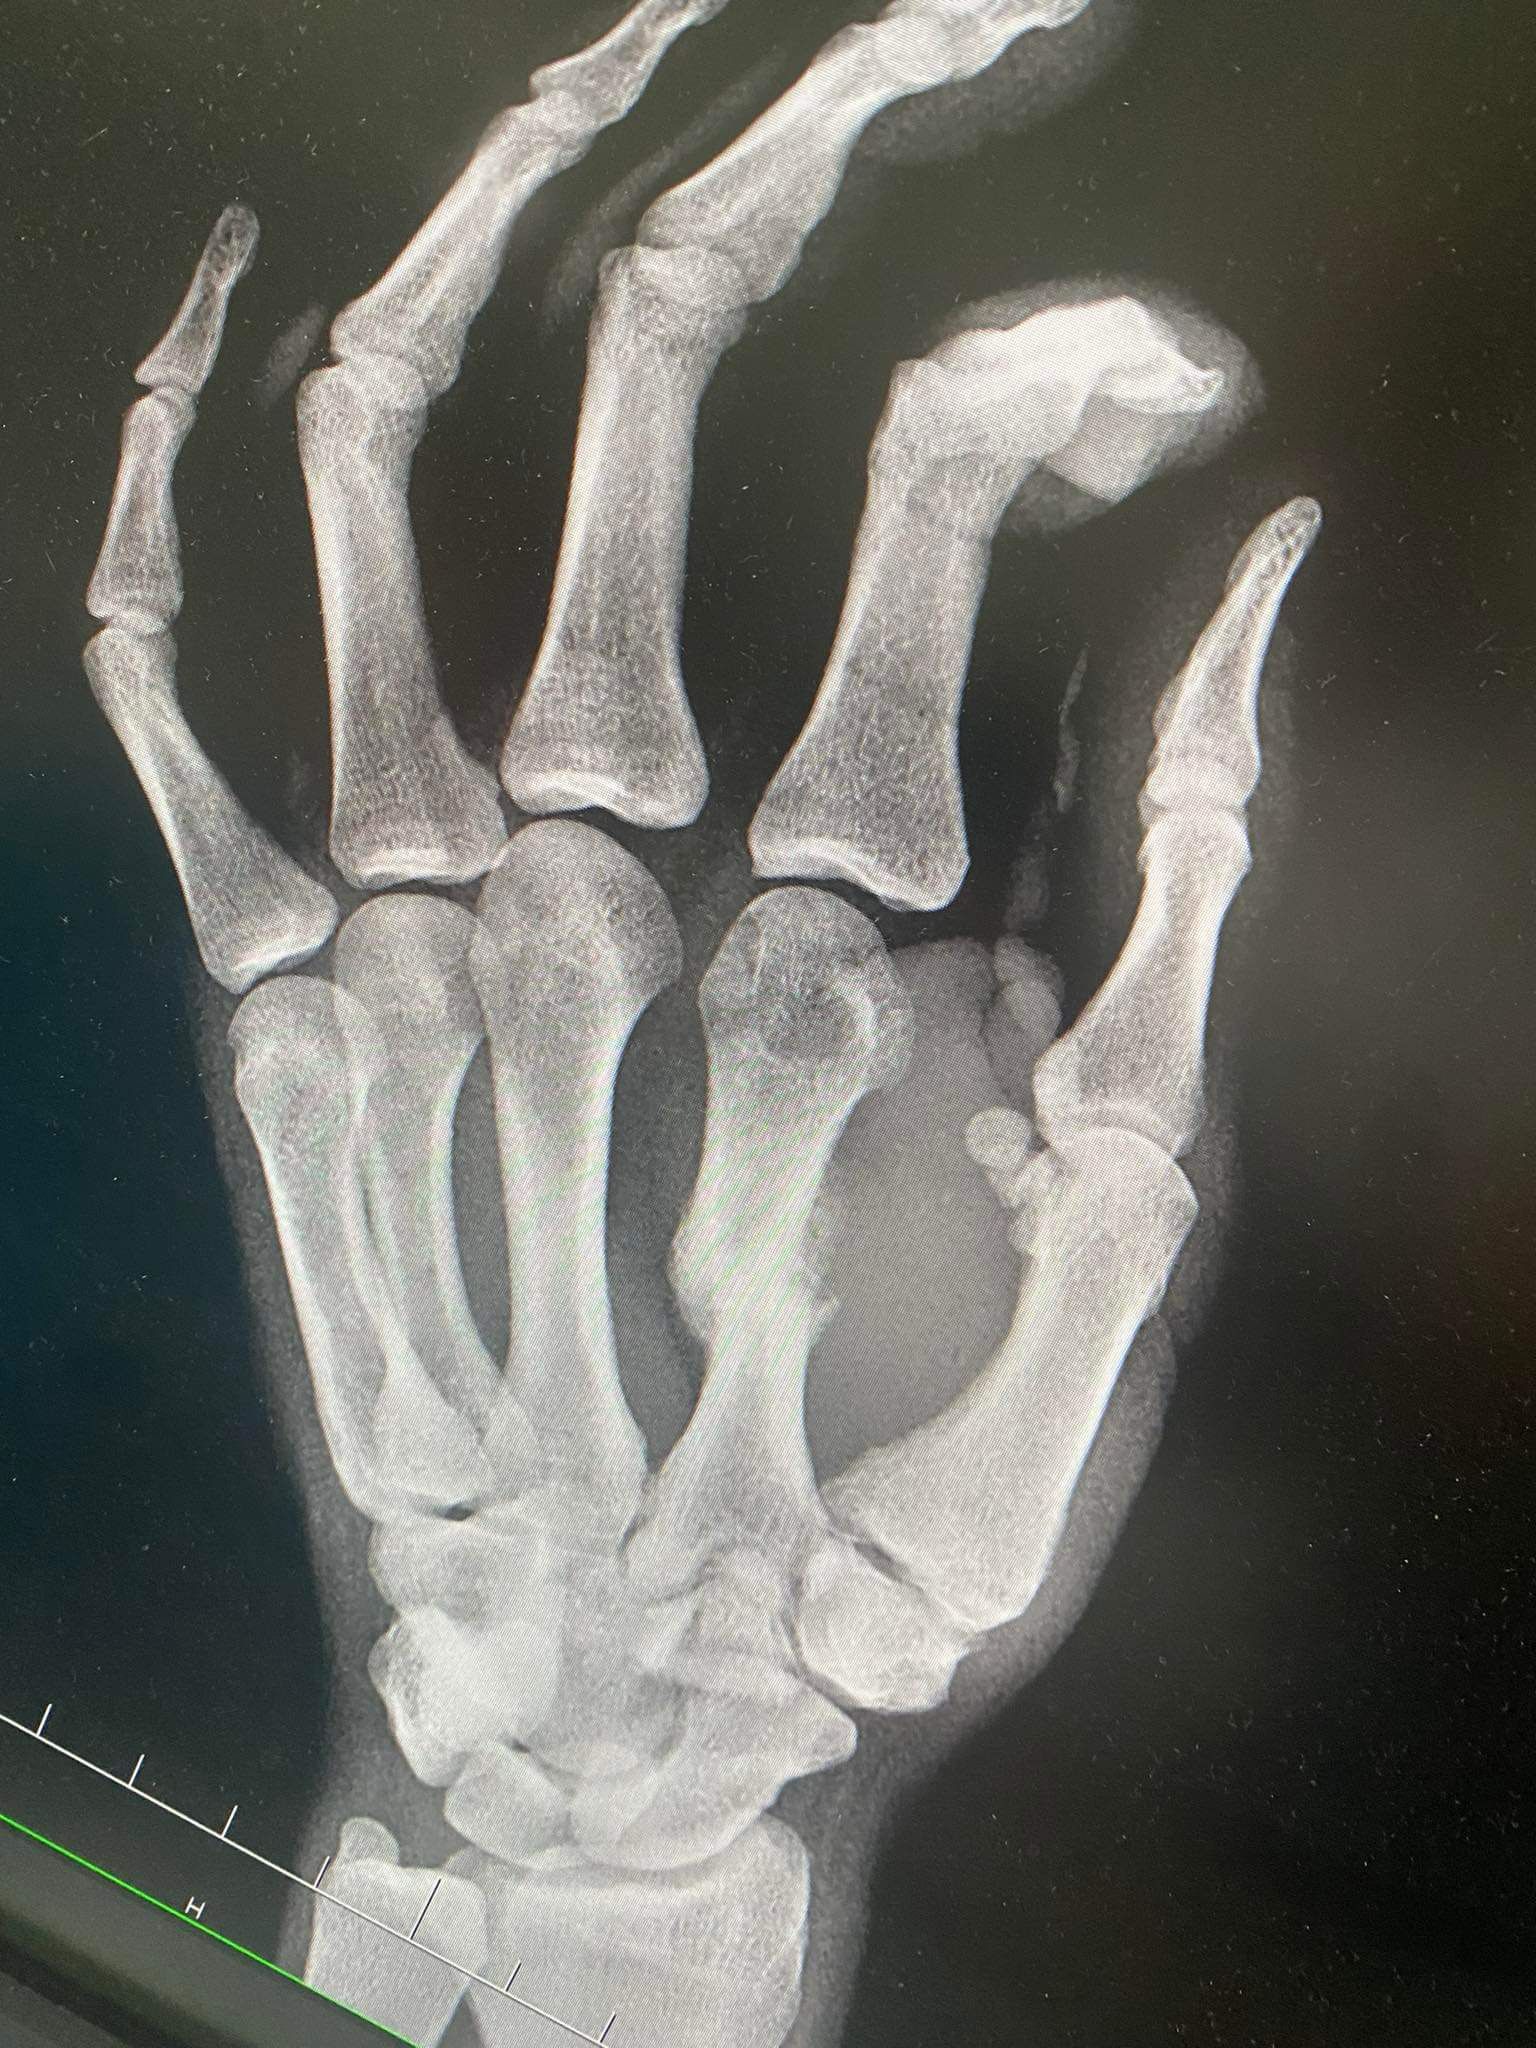

• Zranenie: 4. 6. 2024 – zlomená zaprstná kosť

• Operácia (osteotómia): 27. 10. 2024

Osteotómia je chirurgický zákrok, pri ktorom sa kosť prerezáva a presne nastaví tak, aby mohla správne zrast. Po takejto operácii predstavuje hlavnú výzvu najmä kvalita zhojeného kostného tkaniva, opuch, bolesť a obmedzenie pohyblivosti. Práve terapia LIMFA tu zohrala kľúčovú úlohu.